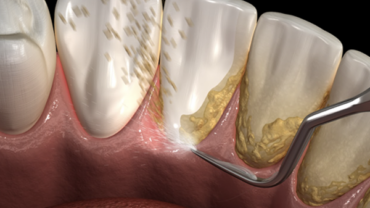

Le Détartrage Consiste à ôter le tartre des surfaces dentaires. Il s'agit d'une substance dure qui recouvre les dents et qui peut entraîner des complications…